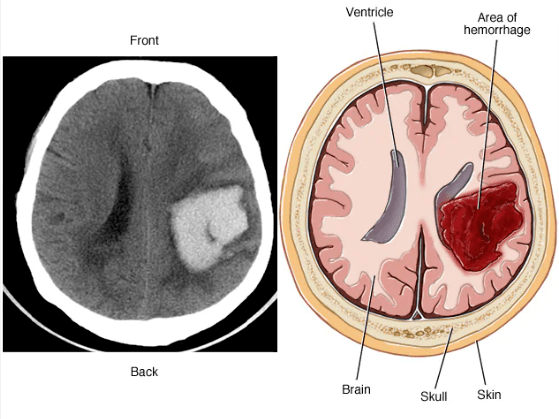

脑出血的危害不可小觑。据医学研究数据显示,脑出血的致残率高达40%至80%,而且近50%的患者在发病后一个月内就会死亡。当脑出血发生时,脑血管破裂血液进入脑实质,可导致颅内压增高,损害周围脑细胞,进而引发严重的神经功能障碍,严重的脑出血可导致肢体瘫痪、失语、昏迷、甚至病危和死亡。而早期诊断与及时合理治疗可以扭转不良结局,而延误诊断与不当治疗则可导致不良结局。

最新的研究提示不同部位不同出血量有助于判断脑出血的预后:脑叶40.5mL,壳核/外囊32.5mL,内囊/苍白球5.5mL,丘脑6.5mL,小脑17mL,脑干3mL以下有良好结局;而脑叶48mL,壳核/外囊41mL,内囊/苍白球6mL,丘脑9.5mL,小脑22mL,脑干7.5mL以上有不良结局;脑叶出血体积超过89.5ml,壳核/外囊体积超过42mL,内囊/苍白球体积超过21mL者其死亡风险较高[2]。脑室内出血因可引起阻塞性脑积水,常预后不良。

出血位置出血量与预后关系